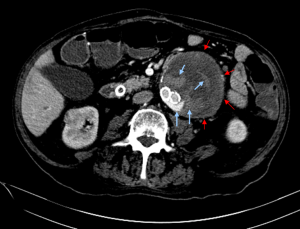

- Type II endoleak – Results from a blood vessel that is filling the original aneurysm sac around the graft. Three blood vessels that are commonly implicated in type II endoleak are lumbar arteries, accessory renal arteries and the inferior mesenteric artery. An important principle to understand regarding type II endoleaks is that there should always be two arteries visible entering the aneurysm sac – one artery is the one carrying blood to the sac and the other taking it out (otherwise the sac would always grow and rupture).

Two signs during imaging suggest an endoleak. The first is continued aneurysm expansion despite treatment. The second is extravasation of contrast material from within the artery (or graft) into the aneurysm sac. When this occurs the type of endoleak needs to be delineated. This is done by examining the endoleak location, looking for a blood vessel entering the aneurysm sac and making sure the stent is complete (without overt flaws in the stent). Another tip for proper CT imaging of endoleak is to use delayed images (typically at 70 seconds after contrast injection). At this time equilibrium has been achieved. A common mistake is mistaking calcifications and contrast extravasation on CT. Therefore a comparison of the contrast and non-contrast images should be made.